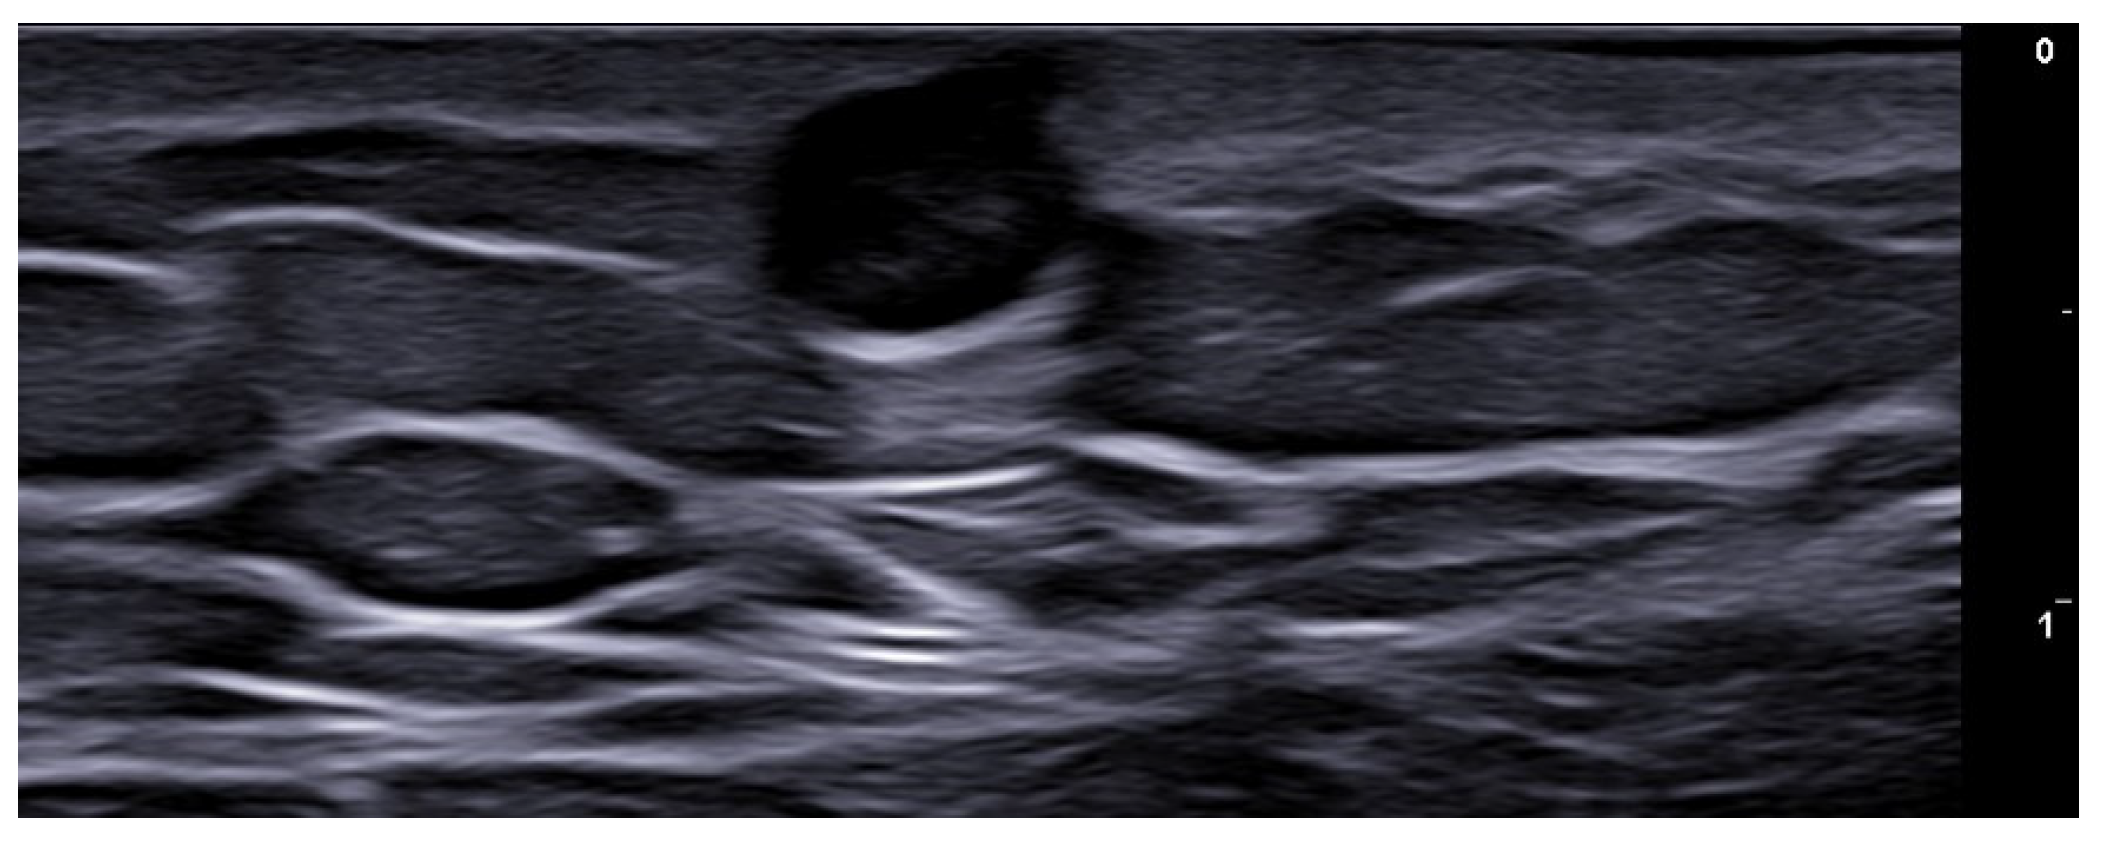

- Berritto, D.; Iacobellis, F.; Rossi, C.; Reginelli, A.; Cappabianca, S.; Grassi, R. Ultra high-frequency ultrasound: New capabilities for nail anatomy exploration. J. Dermatol. 2017, 44, 43–46. [Google Scholar] [CrossRef]

- Szymoniak-Lipska, M.; Polańska, A.; Jenerowicz, D.; Lipski, A.; Żaba, R.; Adamski, Z.; Dańczak-Pazdrowska, A. High-Frequency Ultrasonography and Evaporimetry in Non-invasive Evaluation of the Nail Unit. Front. Med. 2021, 8, 686470. [Google Scholar] [CrossRef]

- Michelucci, A.; Dini, V.; Salvia, G.; Granieri, G.; Manzo Margiotta, F.; Panduri, S.; Morganti, R.; Romanelli, M. Assessment and Monitoring of Nail Psoriasis with Ultra-High Frequency Ultrasound: Preliminary Results. Diagnostics 2023, 13, 2716. [Google Scholar] [CrossRef]